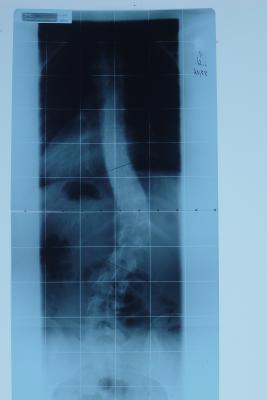

Im Prinzip sieht mein Röbi dem von BZebra recht ähnlich (viewtopic.php?t=1853), nur eben 47° Cobb und spiegelverkehrt (thorakolumbaler Bogen nach rechts). Der Scheitel liegt bei TH12 (ich glaube, bei BZebra niedriger??). Eine Krümmung oberhalb des thorakolumbalen Hauptbogens ist kaum vorhanden, eigentlich geht es nur wieder zurück in die Mitte, der Rest der BWS ist grade...

Starke Hüftprominenz links.